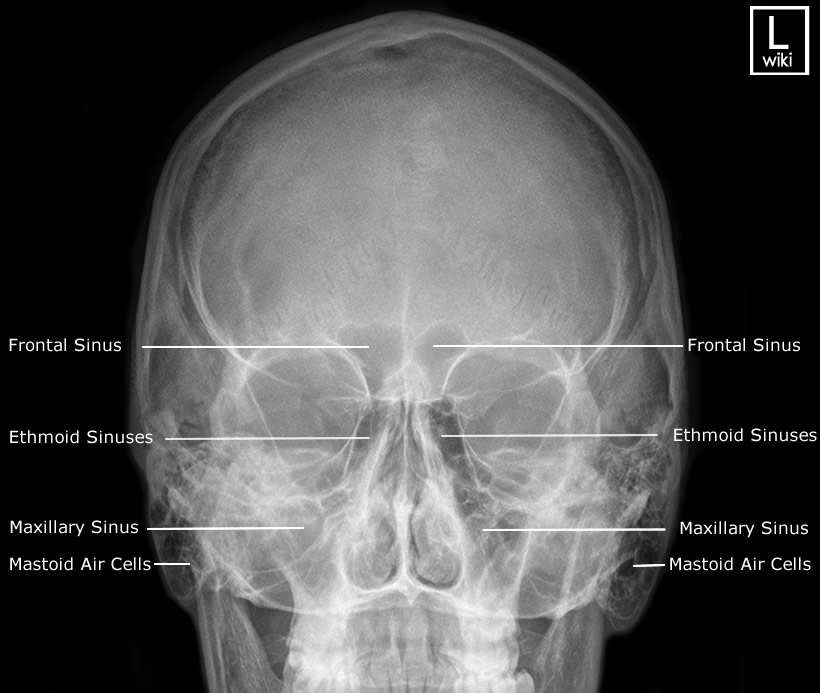

Download scientific diagram | Proyección de Waters: aumento de densidad de partes blandas de los senos maxilares (estrella) y presencia de masa en la faringe (flecha). from publication: Pólipo.. Citation, DOI, disclosures and article data. The Caldwell view is a caudally angled radiograph, with its posteroanterior projection allowing for minimal radiation to the orbits. This view may be used in imaging of the skull or facial bones depending on the clinical indications.

Proyección de Caldwell Wikiwand

RADIO ANATOMIA CRANEO

Senos Paranasales Imagenología

Semiologia y radiologia de senos paranasales